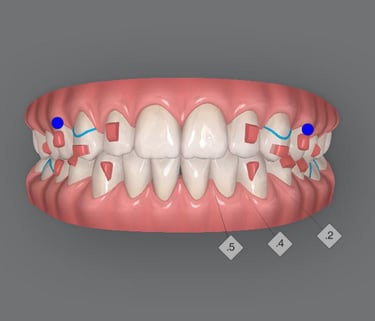

Teeth Crowding

Experience the transformative power of Shrine's Invismile in addressing teeth crowding. Our specialized techniques ensure precise alignment, unveiling a confident and beautifully corrected smile. Say goodbye to crowding with Shrine's Invismile.